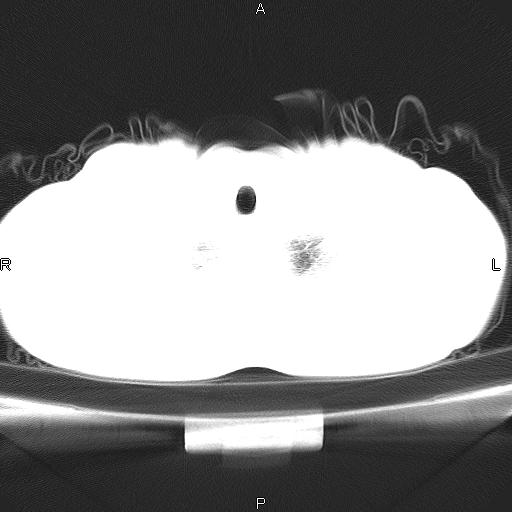

患者,男。50岁。近几日有咳嗽症状,无其他不适,既往病史无,考虑膈疝。请前辈们看看指导指导。

膈膨升,左下肺通气不良,膈肌好像还完整。

符合隔膨升,膈肌较完整。